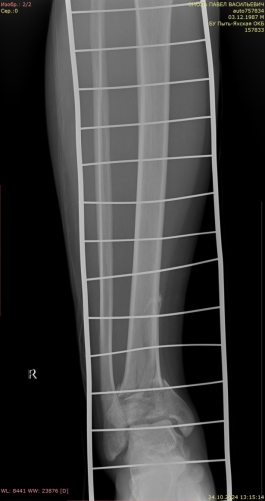

2) Мужчина, 57 лет. В результате падения бревна на область голени получил травму — открытый оскольчатый перелом верхней трети диафиза правой большеберцовой кости со смещением отломков (рис. 4).

Рис. 4.